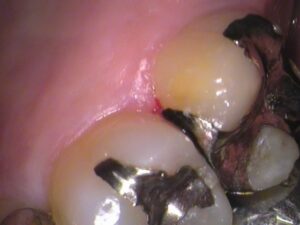

う蝕検知液という、虫歯を染色するお薬をつけてみると、

手前の歯との間の所が赤く染まっています。

レントゲン写真で銀歯の隙間が黒くなっていたところですね。

やはり虫歯がありました。

また、

セメントが入っていた内部にも虫歯が広がっていました。